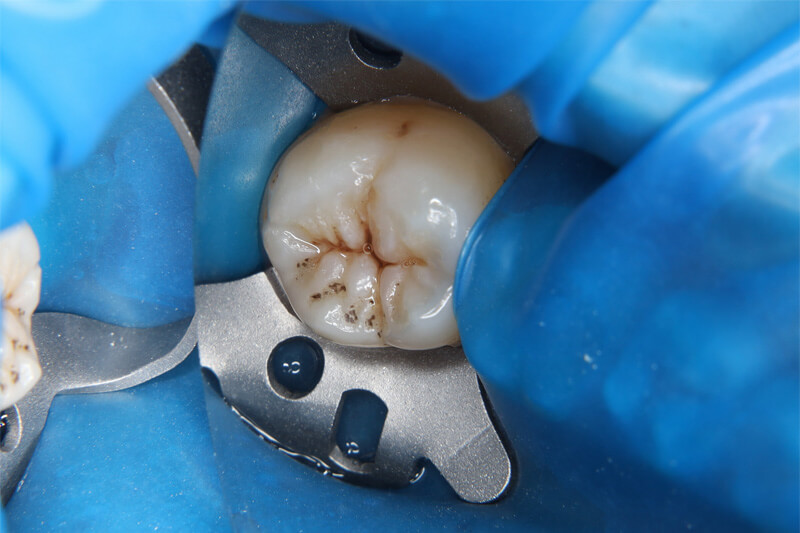

ラバーダム防湿とは、治療する歯のみをゴムのシートで隔離し、唾液や歯肉などからの滲出液中の細菌が、治療中の歯の歯髄腔(歯の神経や血管が通っているお部屋)に入り込んでしまうのを防ぐための処置です。唾液の中には大量の細菌が含まれているため、その唾液が根管内に入ることで複雑感染が起こってしまうことも知られています。

また、根管治療では非常に細かい器具や次亜塩素酸ナトリウムなどの強い薬剤も使用するため、それらが喉の方に流れていかないように予防することもできます。